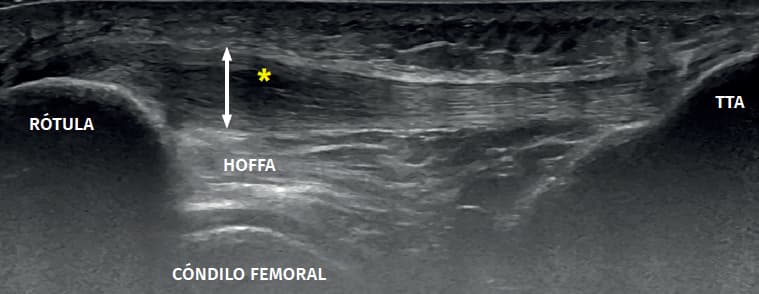

Disponemos de ecógrafos de alta resolución para la evaluación y tratamiento de las patologías músculo-esqueléticas, lo que nos permite conocer la situación del tejido, la localización exacta del daño y el abordaje de los tratamientos invasivos con precisión y seguridad.

La realización de la técnicas de Fisioterapia Invasiva de manera ecoguiada nos permite alcanzar una gran precisión en el abordaje de la estructura diana así como la seguridad de no pinchar estructuras vasculares, viscerales o neurales que podemos encontrar próximas a la zona a tratar.